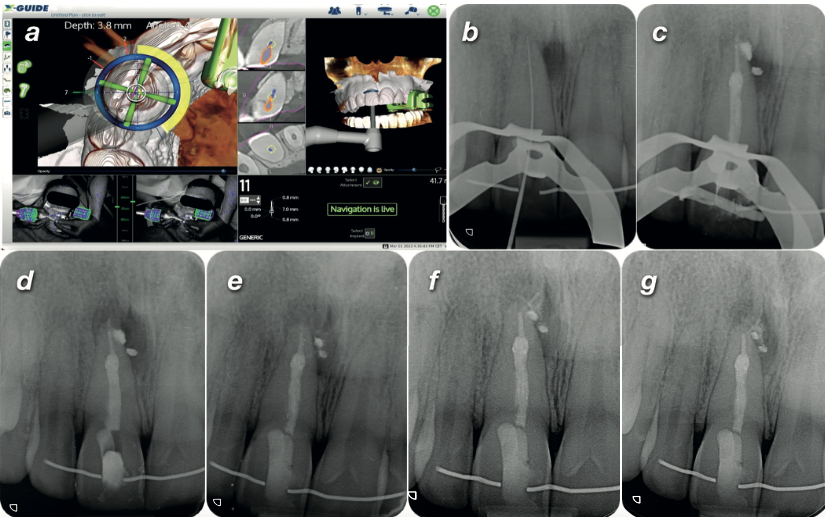

Live dynamic navigation screen and follow-up radiographs

Endodontics Navigation CS 8100 3D

A Calcified Canal, a Failed Access, and Dynamic Navigation to the Rescue

When the first attempt went wrong, high-resolution CBCT and live-guided navigation saved the tooth — complete healing at 12 months.